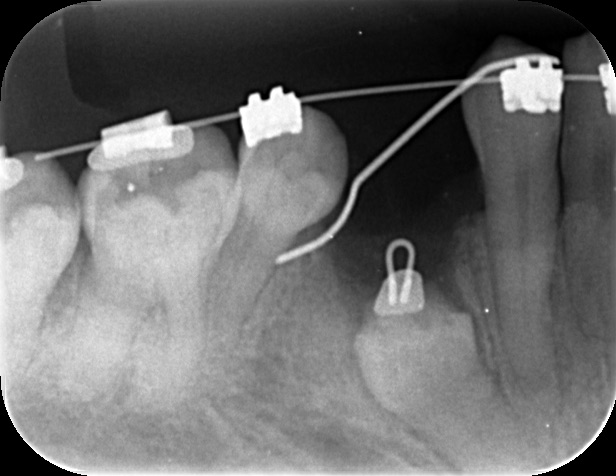

右下4番の根尖に過剰歯を認め、矯正治療による歯の動きを邪魔してしまっているとともに4番の根尖を吸収しているように思われたため、抜歯をして過剰歯を利用。

マイクロスコープの拡大明視野下で矯正用のボタンをセットする。 歯冠の形が歪で周囲の歯槽骨に引っかかってなかなか萌出してこなかったため、少しだけ亜脱臼させたあと矯正力をかける。